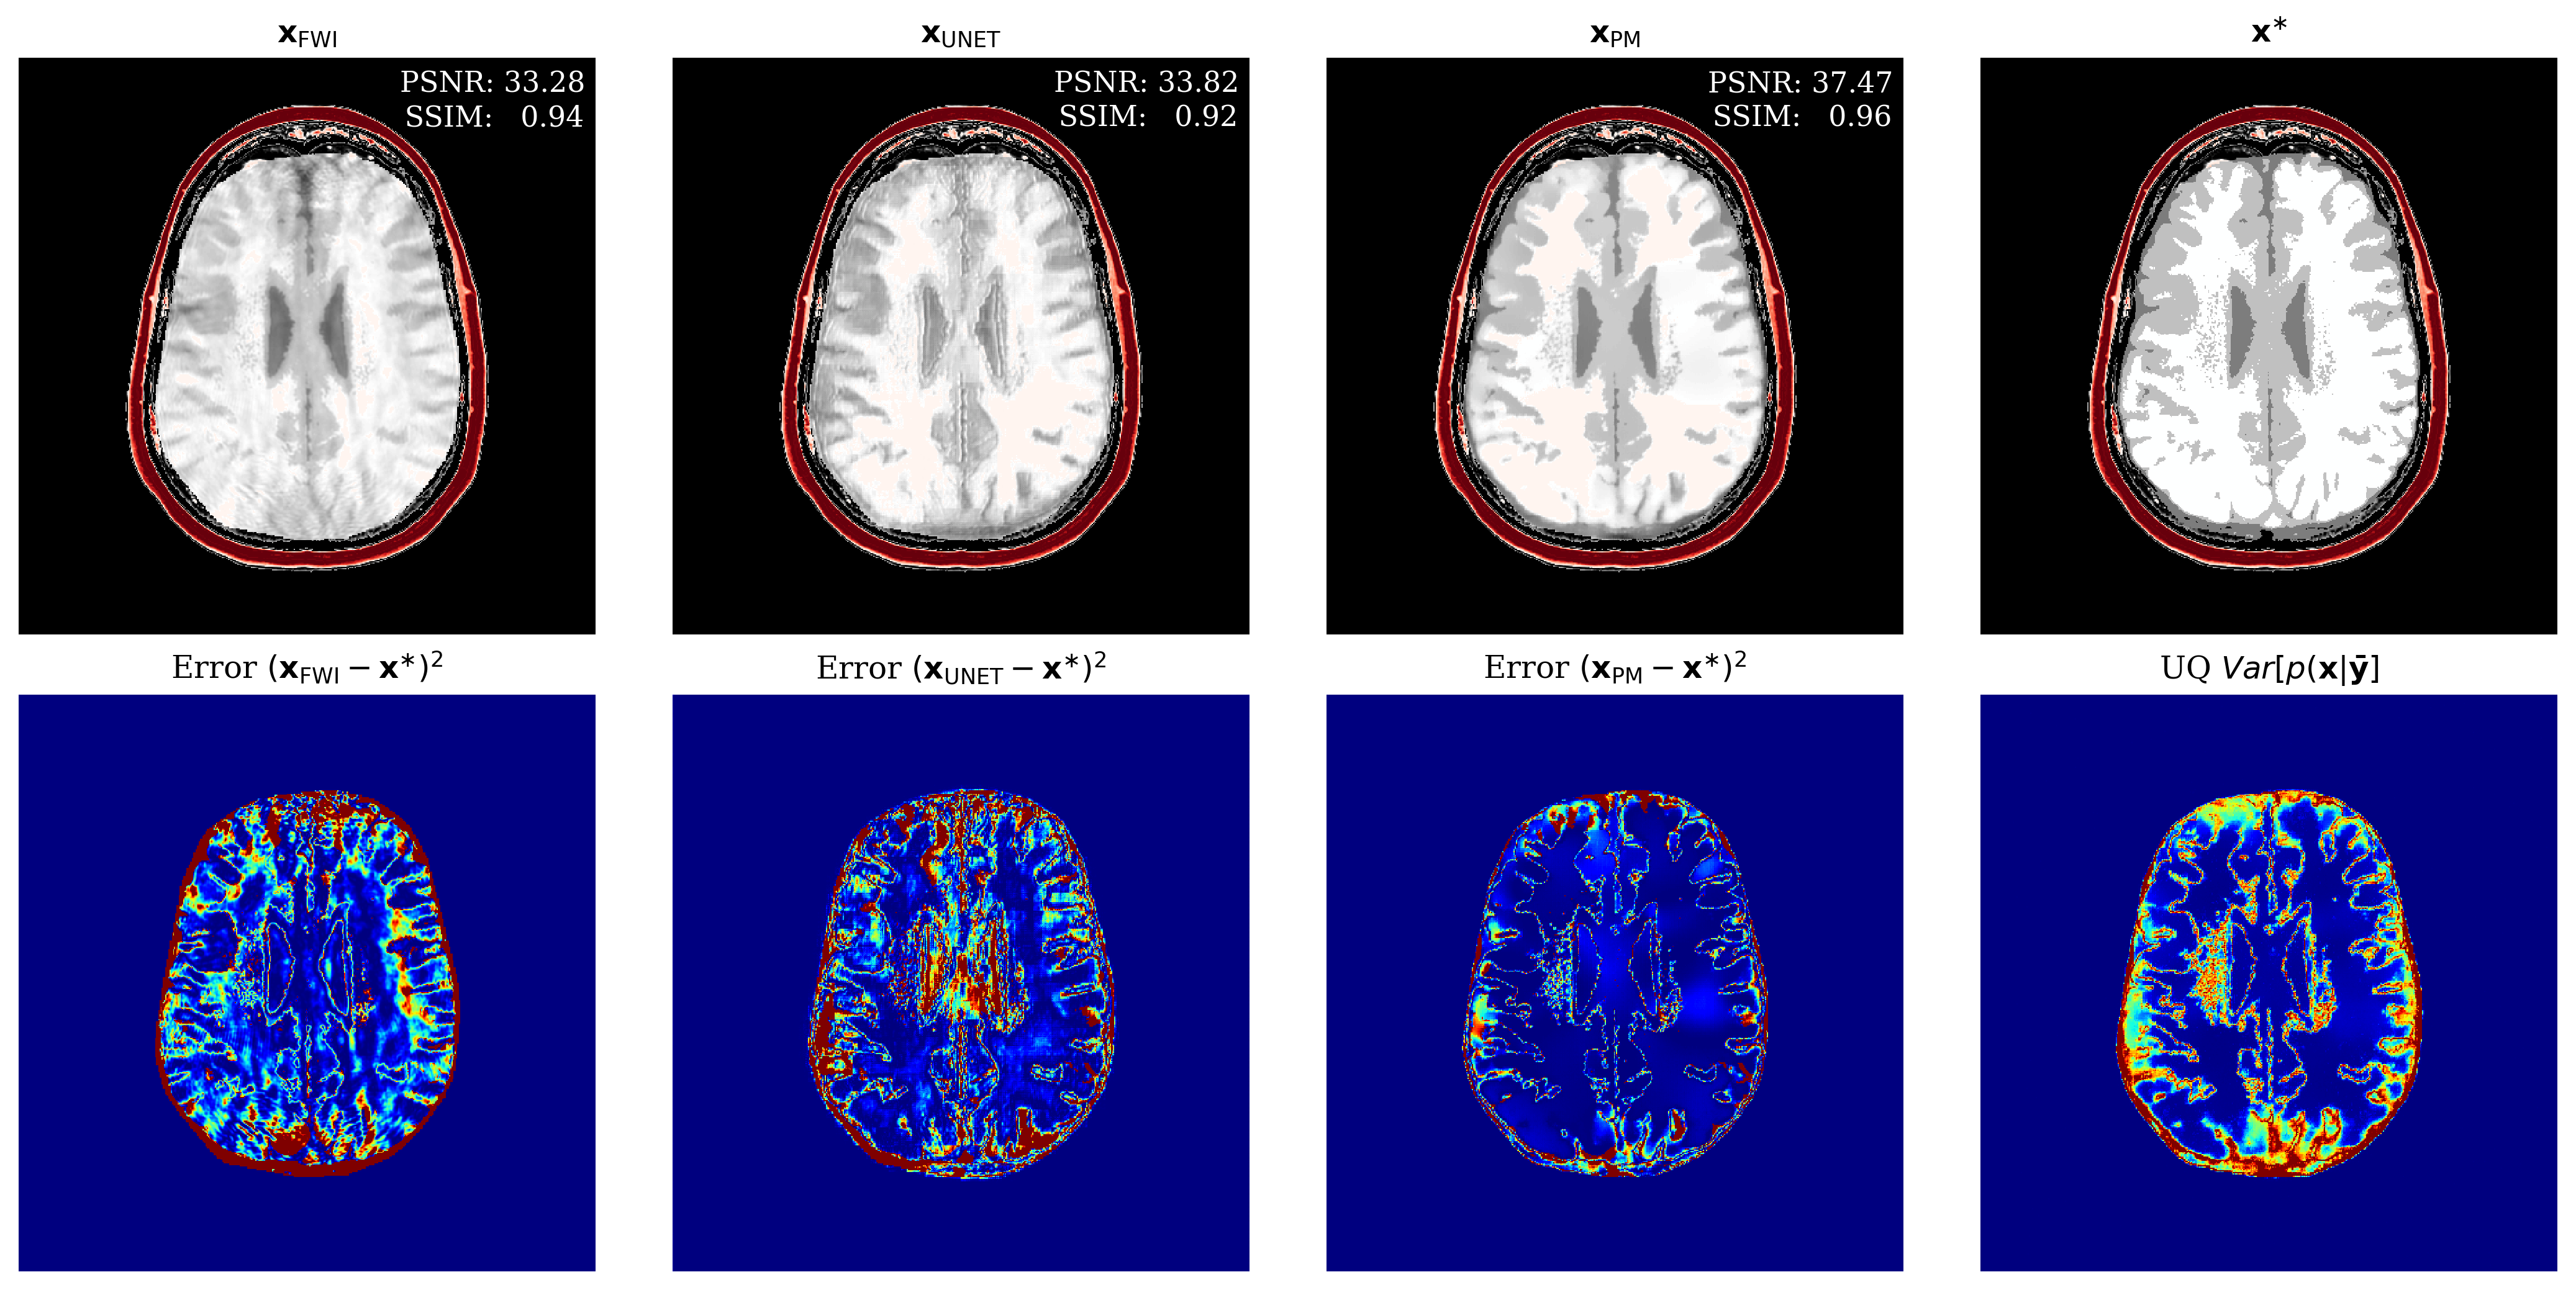

To assess the performance of our reconstruction, , we compare with two baseline methods, namely physics-only FWI, yielding obtained by gradient descent, and a supervised U-Net Ronneberger et al. (2015) trained on the same data pairs as our method. Compared to the learned methods, which incur off-line training costs prior to inference, FWI is computationally intensive since it requires calls to the forward and gradient for each source while our method only requires one gradient per source. Refer to Appendix 4.3 for FWI and network training hyperparameters.

fig:compare

From Figure LABEL:fig:compare, we make the following observations: (i) our result contains fewer artifacts compared to FWI; (ii) it performs better than U-Net; (iii) it captures the full posterior yielding pointwise variances that correlate well with error; (iv) due to averaging over posterior samples our result blurs a few details as compared to FWI. For a more quantitative comparison of the reconstruction quality, refer to \tablereftab:timing in which the average quality metrics for peak signal to noise ratio (PSNR); structural similarity index metric (SSIM); and root mean squared error (RMSE) are computed from unseen test slices. Our method shows high performance on all metrics while keeping the online inference time significantly lower than the FWI method. For more direct comparison, we avoided measurement noise.

| Method | Timing (seconds) | PSNR | SSIM | RMSE |

|---|---|---|---|---|

| FWI () | 2100 | 33.25 | 0.9450 | 0.0215 |

| Supervised UNet () | 44.8 + 0.02 | 35.63 | 0.9332 | 0.0168 |

| Our posterior mean () | 44.8 + 3.23 | 38.67 | 0.9646 | 0.0119 |